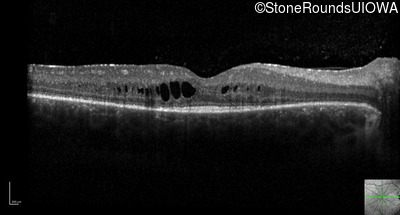

Optical Coherence Tomography - Right - 20/30 -2

Exemplar / OCT Stack